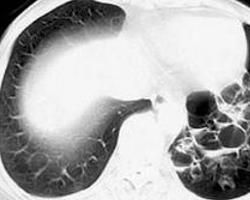

2、CT能分辨出普通X線中不能顯示的肺部結構,且經CT引導下進行經皮肺活檢定位準確安全度大。